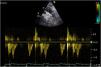

All prosthetic valves create a certain degree of obstruction compared to native valves depending on their design, size, and annular position (intra/supra), resembling stenosis. It is advisable to consult expected gradients for the diameter and model of the prosthesis (appendices 1 and 2).31–35 Therefore, it can be difficult to differentiate hemodynamic obstruction from a mild pathological dysfunction and prosthesis-patient mismatch (PPM) or mismatch (Table 3, Fig. 4, video 4 of the supplementary data).36

In the aortic position, the triangular morphology of the Doppler velocity contour with a short acceleration time provides us with information of normal functioning. As obstruction progresses, the Doppler velocity contour will become more rounded, until it reaches a delayed peak flow (Fig. 4).

Figure 4.* Pulsed-wave Doppler sample volume very close to the prosthesis. # Stenosis additionally confirmed by the EOA compared with reference values if valve type and size are known. ** Pulsed-wave Doppler sample volume distant (apical) from the prosthesis. AT, acceleration time; DLVOT, diameter of the LVOT; DVI, Doppler velocity index or nondimensional functional index; EOA, effective orifice area; indexed EOA, EOA divided by body surface area; LVOT, left ventricular outflow tract; PPM, prosthesis-patient mismatch; VTI, velocity-time integral.

Modified from Zoghbi WA, et al.